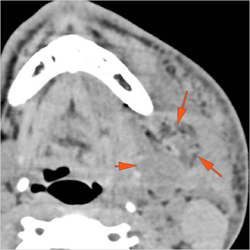

Maxillofacial Trauma - Mandibular

3 cases dealing with injury to the mandibular and surrounding regions.